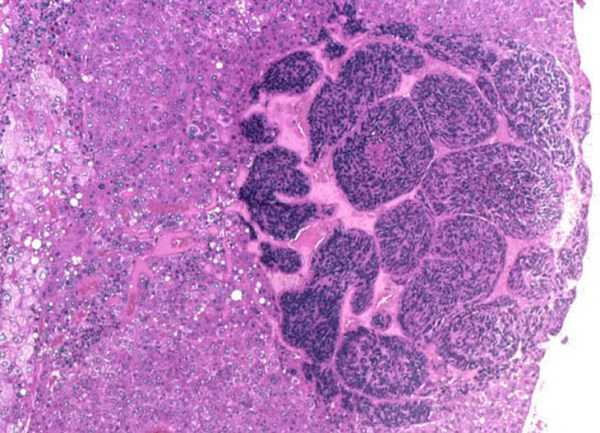

- внешне опухоль выглядит как один или несколько узлов, бескапсульного строения, которые имеют плотную структуру желтовато-белого оттенка и могут продуцировать желчь;

- гепатобластома печени имеет дольчатое строение с участками некроза, которые видны на поверхности.

Рак печени у взрослых и детей обычно классифицируют по гистологическим признакам и делят на 2 морфологические разновидности:

- зародышевый эпителиальный тип. Структура опухоли обозначена 2 типами клеток – фетальными (они мелкие, имеют крупное ядро и склонны к более частому делению) и эмбриональными (они остановили свое развитие на определенном этапе внутриутробного периода и не могут выполнять обычные функции);

- смешанный, эпителиально-мезенхимальный тип. При этом типе в опухоли кроме эпителиальных клеток присутствуют соединительнотканные костные, жировые, хрящевые элементы. Иногда могут также наблюдаться включения микроскопических зародышевых слизистых или мышечных (поперечно-полосатых) структур.